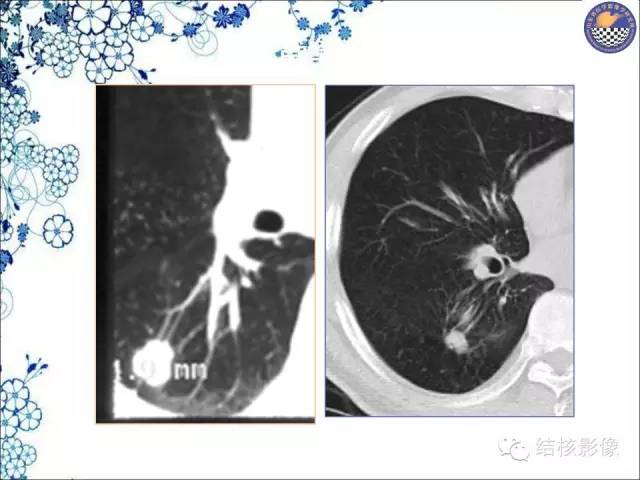

【PPT】肺癌CT高危征象解析